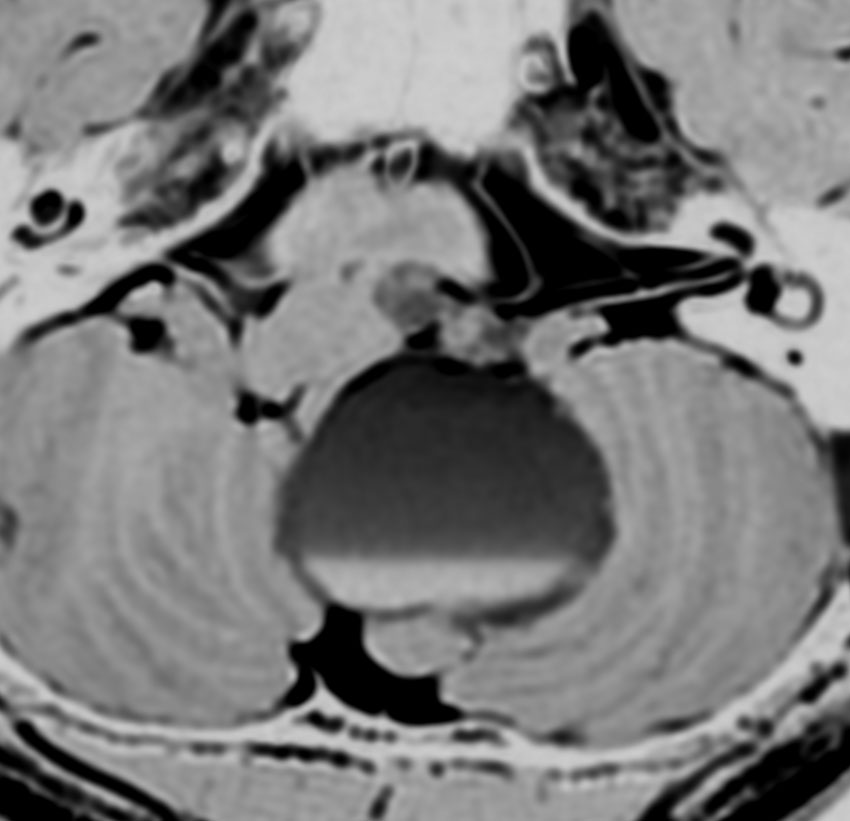

脊髄根 spinal rootから発生した無症候性の副神経鞘腫です。神経根は脊髄前根からでて脊髄の外側から背側へと上行するので,脊髄を横から圧迫するようになります。

徐々に増大しました。手術摘出を行うときに副神経を温存できないと,胸鎖乳突筋と僧帽筋の麻痺が生じます。